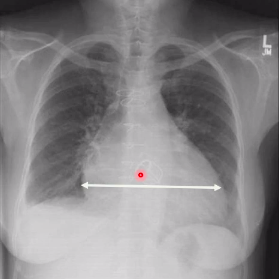

what is this?

costophrenic angle

what is this ?

cardio-phrenic angle